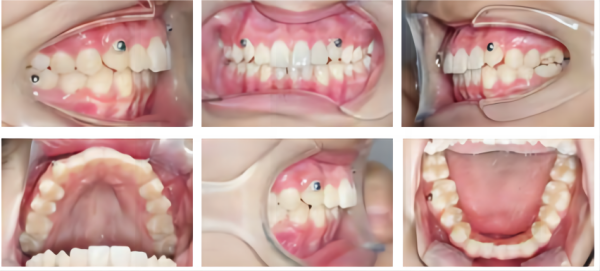

治療中

口腔内写真

2.シザーバイトの程度はそれほど厳しくないので、前シザーバイトの解像度はスムーズに進んだ。 したがって、ワニの固有のスプリント効果は、治療中の咬合干渉を減らすのに役立ちました。

3. VinciSmileは、微細なギャップの制御と計算において優れたパフォーマンスを示しています。 この場合の上顎IPRは安全な範囲内にあり、正確なIPR制御のために医師が必要とする高精度を強調しています。